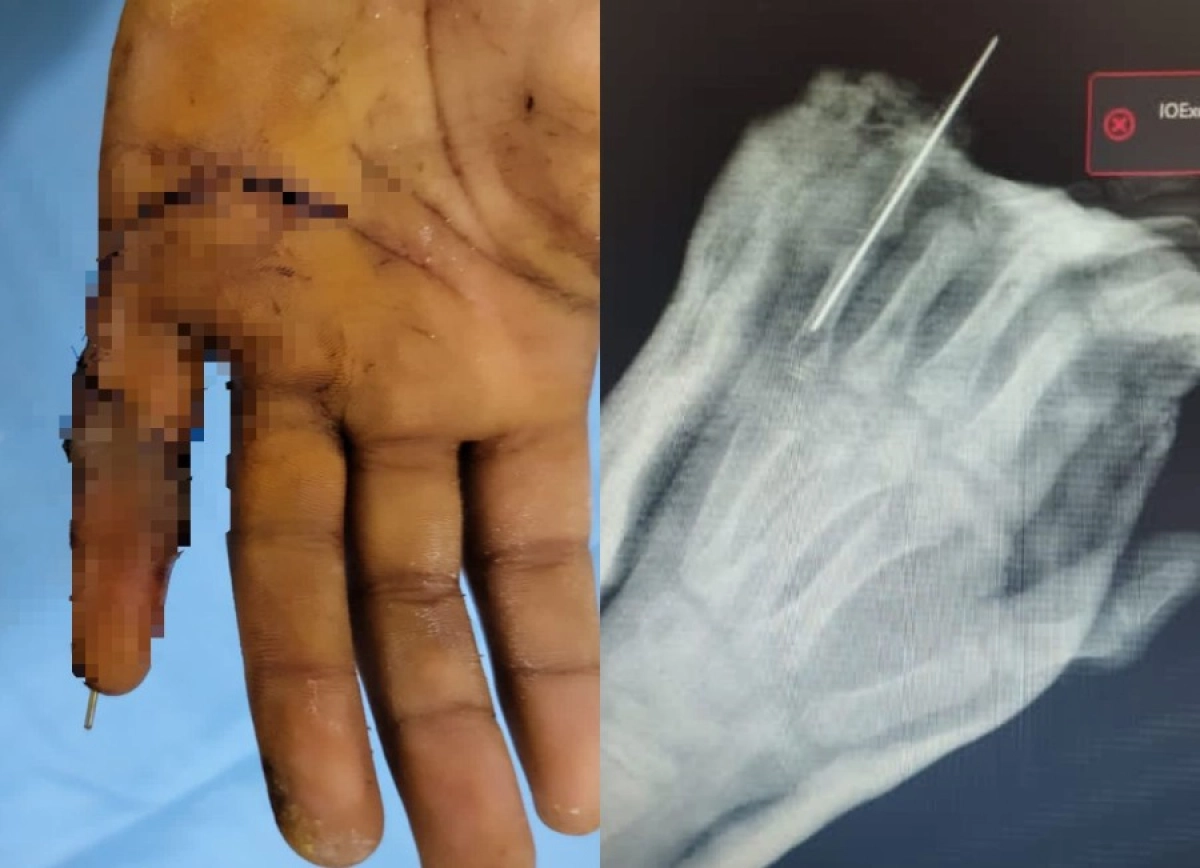

В детской городской клинической больнице №2 Алматы впервые произвели сложнейшую операцию по реплантации пальца кисти ребенку — 9-летнему мальчику пришили палец руки, отчлененный в результате уличной травмы. Экстренную операцию выполнили заведующий отделением травматологии Ерлан Садырбалин совместно с микрохирургами Сергеем Косаревым и Александром Смолянкиным. Шансы спасти палец были крайне малы, передает ИА «NewTimes.kz».

Операция длилась непрерывно около пяти часов. Это очень кропотливая работа. Врачи делали все возможное, чтобы сохранить палец. Они под операционным микроскопом сшивали ткани и сосуды, соединяли поврежденные пальцевые артерии, нервные волокна очень малого диаметра, были восстановлены кость, сухожилия, вены и кровообращение в присоединенном пальце.

Профессионально выполненная реплантация позволила избежать возможных рисков, вернуть подвижность и чувствительность поврежденной части кисти. В течение восьми дней мальчик получал стационарное лечение, палец полностью прижился. Родители мальчика расценивают результат операционного вмешательства настоящим чудом и безмерно благодарны профессионалам своего дела.